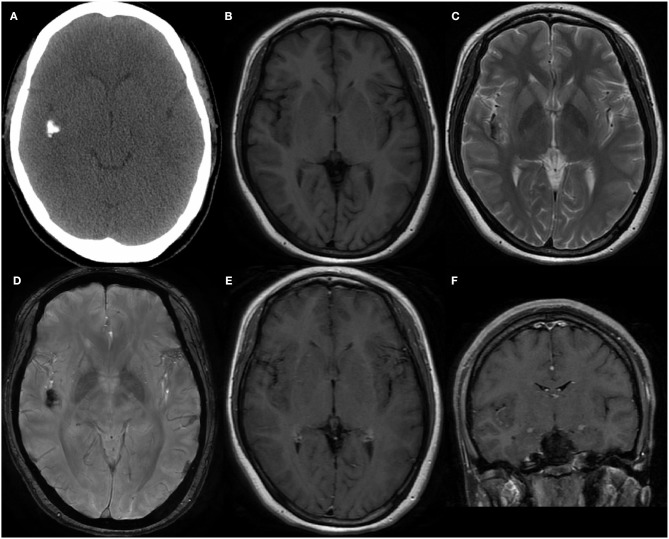

The patient was a 30-year-old homemaker with a 2-year history of seizures before admission. She had previously been treated with a routine antiepileptic (sodium valproate; 1,000 mg per day) for 3 months; however, the drug was weaned off because of its side effect (weight gain). Subsequently, she was prescribed lamotrigine (200 mg per day) and topiramate (75 mg per day) for seizure control, but continued to have occasional seizures, once or twice a month. She had no other neurological deficit or past medical history, and results of systemic examinations were normal. She had no family history of hereditary diseases. Electroencephalography performed after admission detected epileptiform activity in the right cerebral hemisphere. Computerized tomography (CT) demonstrated a calcific lesion in the right Sylvian fissure and posterior part of the insula (Figure 1A). An MRI scan revealed a lesion in the right insular lobe without any dural attachment, which was primarily hypointense on both T1- and T2-weighted MRI (Figures 1B,C). Additionally, the lesion appeared hypointense on susceptibility-weighted imaging (Figure 1D), with no obvious enhancement despite administration of gadolinium contrast (Figures 1E, F). The results of all preoperative laboratory tests were within normal ranges. Preoperatively, low-grade glioma, including oligodendroglioma, and diffuse astrocytoma, was suspected.

Figure 1.

(A) The Computed tomography demonstrated the calcification in right Sylvian fissure and posterior part of insula. (B,C) MRI scans revealed a lesion without dural attachment located in right insular lobe which was mainly hypointense on both T1-weighted and T2-weighted. (D) Lesion showed hypointense on susceptibility weighted imaging. Enhanced MRI showed no obvious enhancement after gadolinium administration in axial (E) and coronal (F) position.